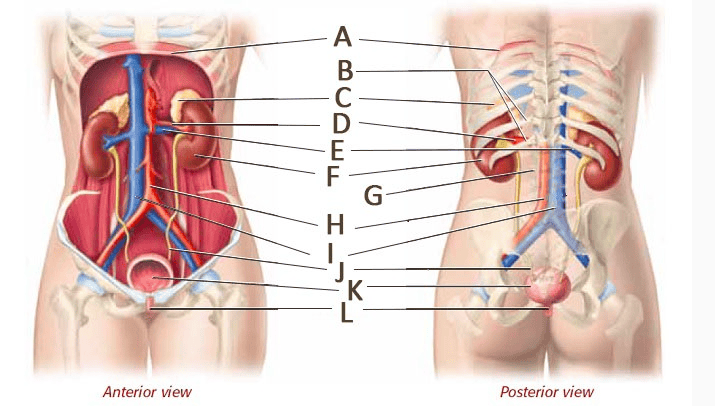

Kidney

Renal artery/vein

Ureter

Urethra

Urinary Bladder (male)

Abdominal Aorta

Common iliac artery/vein

Internal/external iliac artery/vein

Renal Pelvis

Renal cortex

Renal medulla